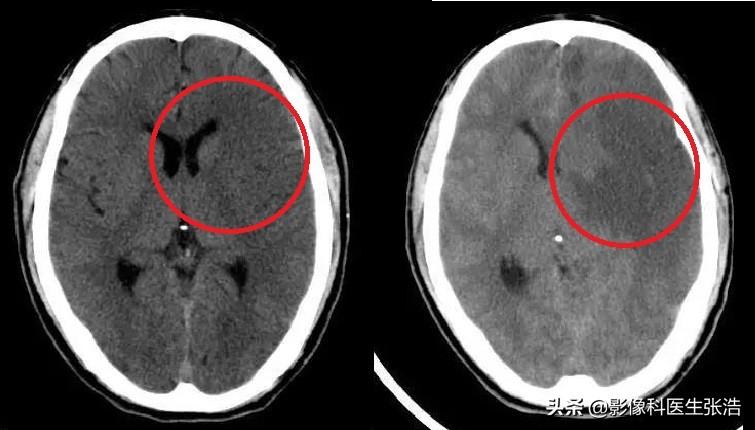

腦梗的診斷主要依據(jù)患者的病史、體格檢查和影像學(xué)檢查,醫(yī)生會根據(jù)患者的癥狀、體征以及可能的病因進(jìn)行初步判斷,并結(jié)合頭顱CT、MRI等影像學(xué)檢查來確診。